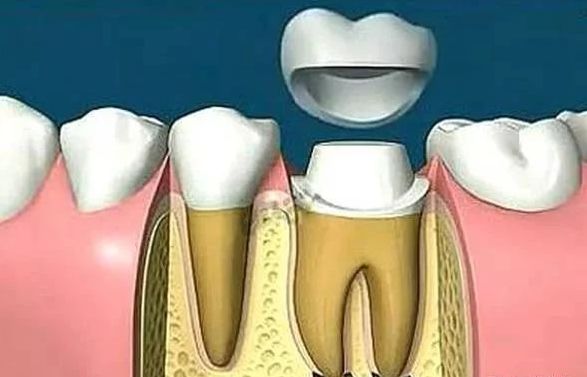

牙齿劈裂怎么办?为什么根管治疗做好还要戴冠?

正因为这些原因,在某些情况下,做完根管治疗还需要戴上牙冠来保护牙齿。

“戴冠”若不够,桩钉来帮忙

当牙齿做完根管治疗,由于牙齿自身的结构及治疗的需要,牙冠中心一般都是空的,这时,如果直接做牙套,其抗折断力很差,一般都需要在牙根上打上桩钉,做出个结实的核,以对抗牙齿使用中的折断力。

对于后牙来说,做完根管治疗之后一定要做上牙冠,否则在承受咬合力量时,牙齿容易出现断裂。少数做完根管治疗的后牙,若是要做单一的牙冠,只需将所剩牙质修补足够,则可不需做桩钉,但若做完根管治疗的后牙是要作为假牙的基牙,则无论牙质所剩多少,最后都能做好桩钉。